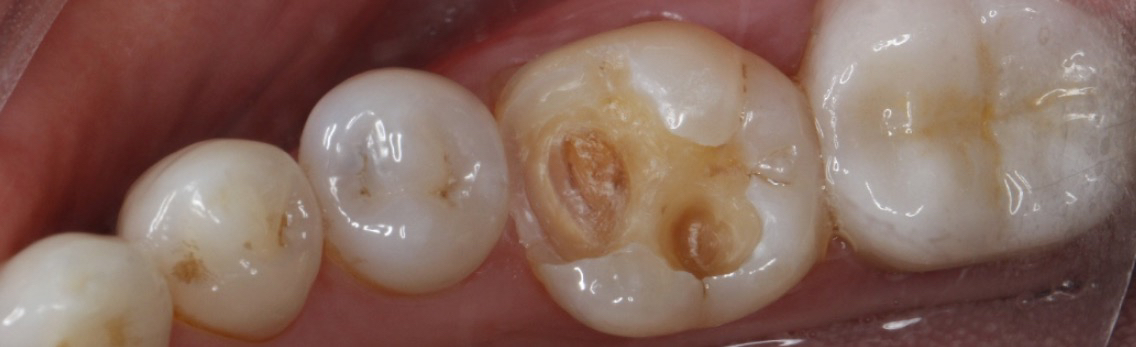

患者因长期忽视口腔卫生,导致一颗后牙出现龋坏,进食时常感到酸痛。经检查发现,龋坏范围较大,但尚未伤及牙髓,医生建议采用嵌体修复。

嵌体修复是一种精准的修复方式,特别适合像患者这样龋坏较深但无需根管治疗的情况。该患者选择了西诺德全瓷嵌体修复,去龋坏,IROOT-BP间接盖髓+光固化玻璃离子+3M流动树脂垫底。基牙预备,排龈,精修,然后CEREC扫描,获取牙齿模型,定制出与缺损部位完全匹配的陶瓷嵌体。嵌体制作完成后,医生将其粘接固定在牙齿上,恢复了牙齿的形态和功能。